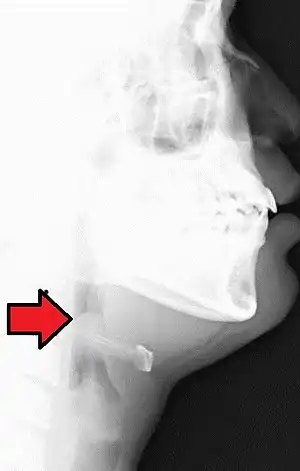

| Lateral radiograph showing the "thumb sign". The diagnosis of epiglottitis was confirmed on subsequent imaging and laryngoscopy. The patient recovered following treatment with prednisone and ceftriaxone | |

In a lateral C-spine radiograph, the sign is caused by a thickened free edge of the epiglottis, which causes it to appear more radiopaque than normal, resembling the distal thumb.